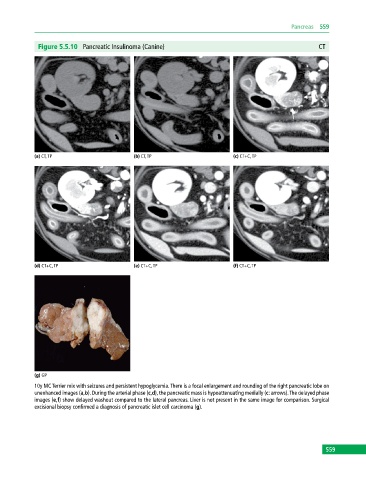

Figure 5.5.10 Pancreatic Insulinoma (Canine) CT

(a) CT, TP (b) CT, TP (c) CT+C, TP

(d) CT+C, TP (e) CT+C, TP (f) CT+C, TP

(g) GP

10y MC Terrier mix with seizures and persistent hypoglycemia. There is a focal enlargement and rounding of the right pancreatic lobe on

unenhanced images (a,b). During the arterial phase (c,d), the pancreatic mass is hypoattenuating medially (c: arrows). The delayed phase

images (e,f) show delayed washout compared to the lateral pancreas. Liver is not present in the same image for comparison. Surgical

excisional biopsy confirmed a diagnosis of pancreatic islet cell carcinoma (g).